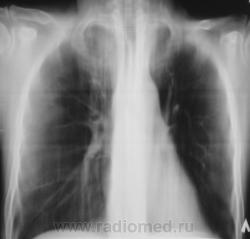

После курса лечения.

После лечения динамика очень хорошая.